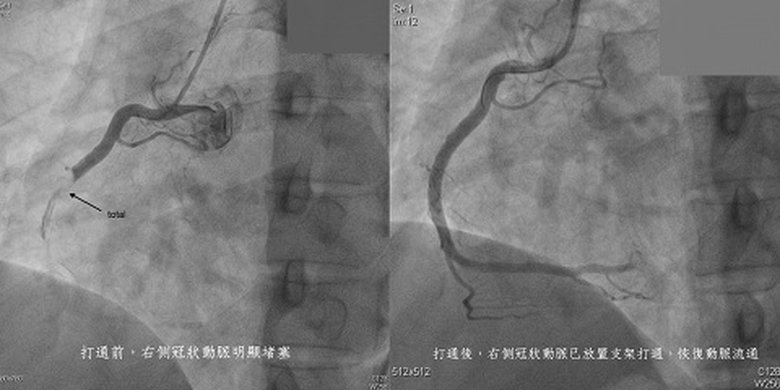

【新唐人亞太台 2022 年 02 月 15 日訊】心肌梗塞發病年輕化,知名導演明金成驚傳51歲因心肌梗塞猝逝,新竹一名39歲男性工程師,開工第一天參加新春團拜,與同事寒暄時卻突然胸痛不已,警急送往東元綜合醫院急診搶救,經心臟加護中心團隊執行心導管手術30分鐘內打通血管,成功救回年輕生命。

東元綜合醫院心臟加護中心主任林育伸醫師表示,急性心肌梗塞主要由於冠狀動脈被血栓(粥樣硬化斑塊)阻塞或冠狀動脈持續性痙攣,致使心肌缺血引發休克甚至死亡。林姓工程師年僅39歲,雖然沒有抽菸習慣,但有高血脂,以及俗稱「隱形殺手」的低密度膽固醇偏高,好在同事相當機警立即送醫,經心導管醫療團隊打通右側冠狀動脈堵塞後,順利保命,康復出院。